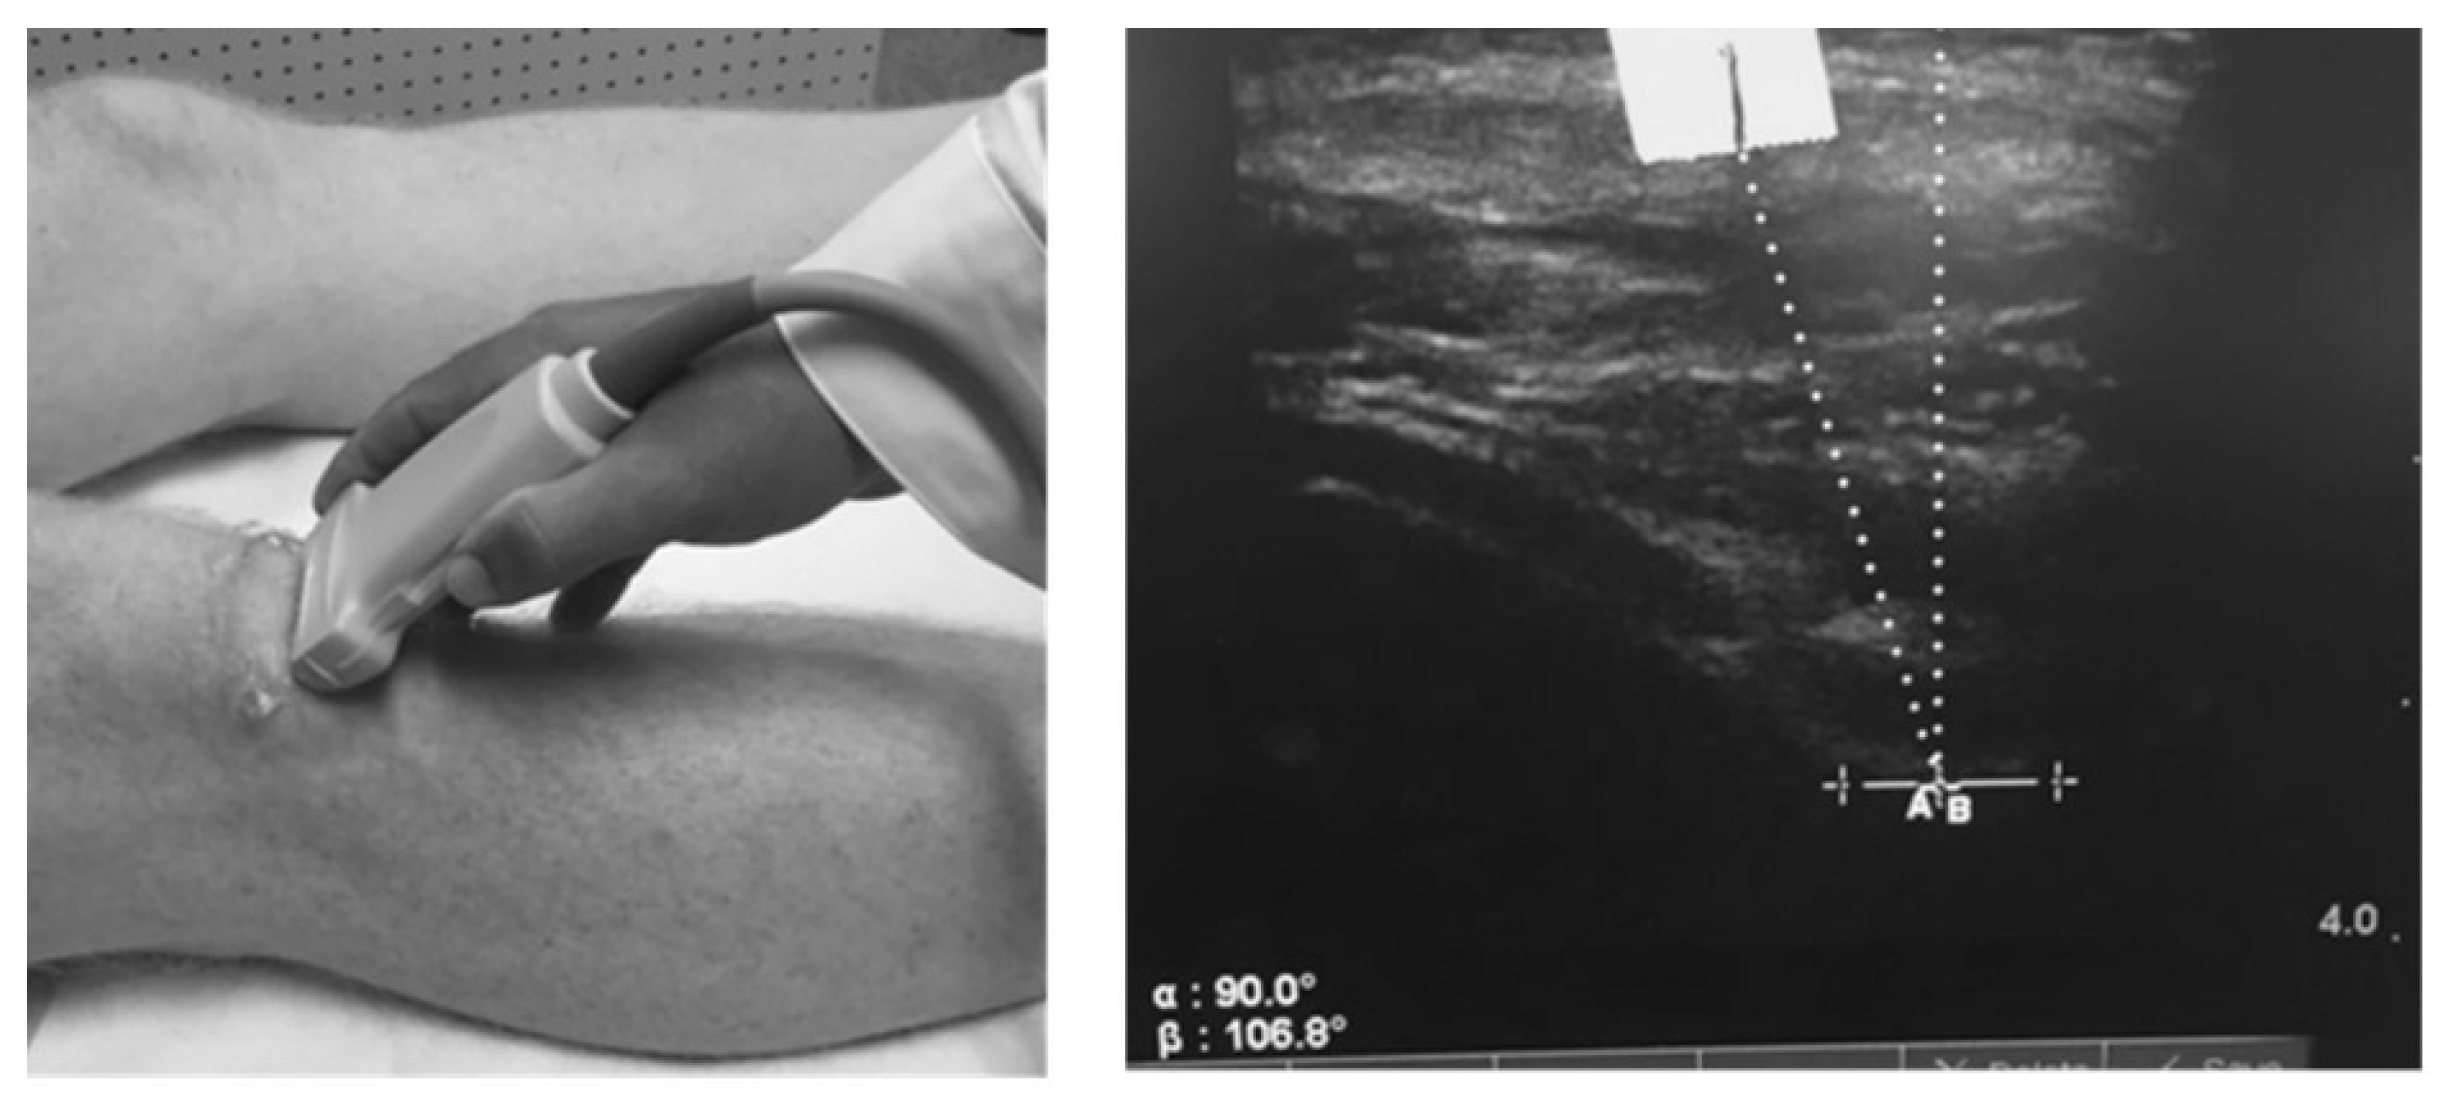

We measured the patella offset angle (RAB angle) using diagnostic ultrasound as described by Anilo et al [38]. Briefly, Anillo et al developed the RAB angle to quantify patella lateralization or medialization relative to the lowest part of the femoral trochlear groove. The RAB angle was measured as follows: 1) a vertical line perpendicular to the lowest aspect of the femoral trochlea and 2) a line from the lowest aspect of the femoral trochlea to the inferior pole of the patella (Figure 1). An angle formed with the line from the lowest aspect of the femoral trochlea to the inferior patellar pole directed toward the lateral aspect of the knee represented patella lateralization. For testing, subjects were positioned in supine with the quadriceps relaxed and the lower extremity in a neutral position. One examiner (D.C.H.) took 2 measures of the test knee. All RAB angles were recorded to the nearest 1/10th of a degree; the average of 2 measures was used for statistical analysis.

Figure 1. Placement of the ultrasound transducer and measurement of the patella offset (RAB) angle. The solid vertical line marker is a reference point for the interior pole of the patella. The perpendicular line represents the deepest aspect of the femoral trochlear. Courtesy of the International Journal of Sports Physical Therapy. .